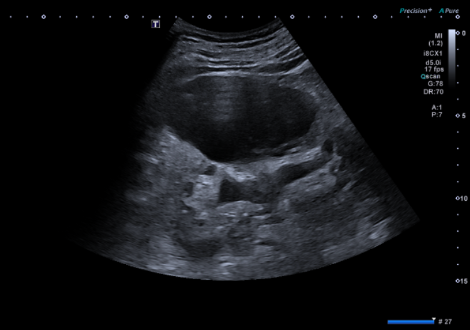

- Ecografía clínica renovesical: Vejiga sin lesiones ocupantes de espacio, sin residuo postmiccional, próstata de tamaño aumentado (56 cc). Ambos riñones con quistes corticales simples, de hasta 9,6 cm en el riñón izquierdo. Sistema excretor derecho no dilatado. Leve-moderada dilatación pielocalicial izquierda. No se evidencian imágenes ecográficas sugestivas de litiasis en pelvis renal.

- Resonancia magnética renal con contraste: hidronefrosis grado II izquierda, secundaria a litiasis obstructiva de 5 mm localizada en el tercio inferior del uréter, inmediatamente caudal al cruce con los vasos ilíacos. Quistes sinusales y simples corticales bilaterales, el mayor de 9,4 cm de eje craneocaudal en el polo inferior del riñón izquierdo. Resto sin alteraciones significativas.

Finalmente, con la evolución de la clínica a dolor lumbar tipo cólico y el conjunto de todas las pruebas complementarias se orienta como cólico renal con hidronefrosis izquierda grado II.